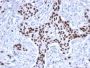

IHC, FFPE (verified), WB (verified)

The specificity of this monoclonal antibody to its intended target was validated by HuProt™ Array, containing more than 19, 000, full-length human proteins. Recognizes a 53 kDa protein, which is identified as p53 suppressor gene product. It reacts with the mutant as well as the wild form of p53. It is a tumor suppressor protein expressed in a wide variety of tissue types and is involved in regulating cell growth, replication, and apoptosis. It binds to MDM2, SV40 T antigen and human papilloma virus E6 protein. Positive nuclear staining with p53 antibody has been reported to be a negative prognostic factor in breast, lung, colorectal, and urothelial carcinoma. Anti-p53 positivity has also been used to differentiate uterine serous carcinoma from endometrioid carcinoma as well as to detect intratubular germ cell neoplasia. Mutations involving p53 are found in many malignant tumors, including breast, ovarian, bladder, colon, lung, and melanoma.Primary antibodies are available purified, or with a selection of fluorescent CF® Dyes and other labels. CF® Dyes offer exceptional brightness and photostability. Note: Conjugates of blue fluorescent dyes like CF®405S and CF®405M are not recommended for detecting low abundance targets, because blue dyes have lower fluorescence and can give higher non-specific background than other dye colors.

MDA-MB-231 Cells. Breast or Colon carcinoma

Higher concentration may be required for direct detection using primary antibody conjugates than for indirect detection with secondary antibody|Immunohistology (formalin): 0.5-1.0 ug/mL for 30 minutes at RT|Staining of formalin-fixed tissues requires boiling tissue sections in 10 mM citrate buffer, pH 6.0, for 10-20 minutes followed by cooling at RT for 20 minutes|Optimal dilution for a specific application should be determined by user